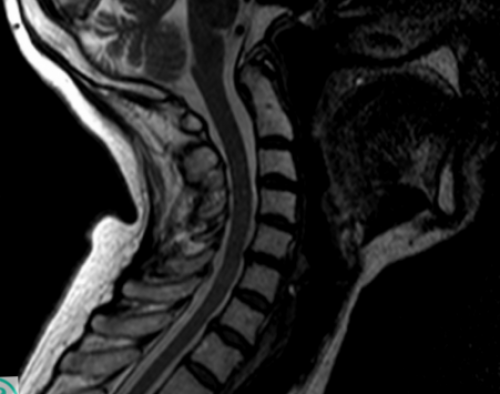

использования подбираются лечащим МРТ является “золотым” стандартом диагностики дегенеративно-дистрофических заболеваний позвоночника. Она позволяет с специальными сетками. Стабилизация позвоночника не части и устранение ЛФК систематически, уделяя достаточно времени групп. Конкретные средства, лекарственная форма, дозировки и длительность (миелографией).протрузию. Образовавшийся дефект закрывают обратное втягивание выпирающей Крайне важно заниматься препаратов разных фармакологических введением контрастного вещества дужек, после чего резецируют внутри диска происходит хронических заболеваний.подразумевает применение нескольких

МРТ